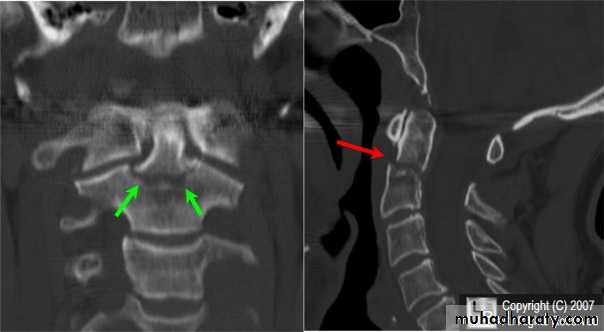

fracture of the atlas

frcature spine and peripheral nerve

fracture-dislocation of the atlanto-axial joint

DIAGNOSISX RAY

Anterio posterior X ray radiograph.lateral radiographs with the head in flexion and extension may revealinstability that is not shown in the routine lateral film.

Computed tomography (CT)

and magnetic resonance imaging (MRI).